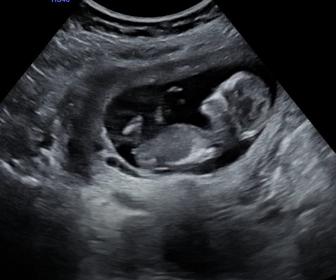

Hello everyone... I got my genderscan today (14 weeks now) but the results weren't convincing for me ... What do you think of it? Boy or girl?

Attachment 38236

your 12 week looked super girly to me, and this is ALL girl!!!! congratsssss

i have a boy 08 and boy 10, you will absolutely loveeee having a girl after all these yrs!!